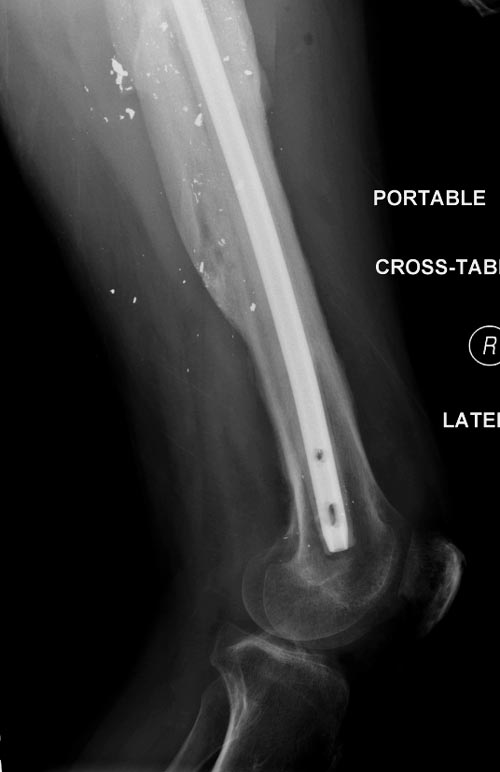

На снимках осложнение огнестрельного перелома бедра поздней инфекцией. 7 лет назад оперирован: правое бедро, сперва на ExFix, затем заменен на гвоздь, а левая - гвоздь при поступлении.

Беспокойство проявил недавно, по поводу жалоб на боли сделано МРТ и дренирование абсцесса терапевтами. Мы удалили гвоздь, сделали I&D, рассверливание канала, и ввели гвоздь с антибиотиком. Для гвоздя использовали стерильную трубку-форму, а антибиотик по 1.0 Tobramycin c Vancomycin.

В замкнутом без перелома пространстве во время риминга повышается давление внутри канала, и имеется риск тромбообразования. Для профилактики и для дренажа - каннюлированный винт 6.5 мм в дистальной части бедра. Обработку заканчивают культурой из раны и канала. Иногда процедуру надо будет повторить.

Рекомендуется: антибиотический гвоздь на цементе. Нагрузку можно разрешить сразу, перелом сросся давно!

Гвозди с антибиотиком все custom made, т.е. делаются во время операции. Диаметр зависит от внутреннего диаметра канала. Обычно достаточным бывает 10 мм, и редко применяется готовые гвозди для армирования цемента. Трубка в 10 мм для плевральной полости как форма и армирование 2.8 или 3.2 мм guide wire для гвоздей, которая срезается по длине, на конце делается петля для облегчения удаления.

В представленном случае, из-за большого диаметра первичного гвоздя (13мм) применили готовый гвоздь в 11 мм, а трубка с внутренним диаметром 16 мм.

Здесь представлены примеры подготовки гвоздя....